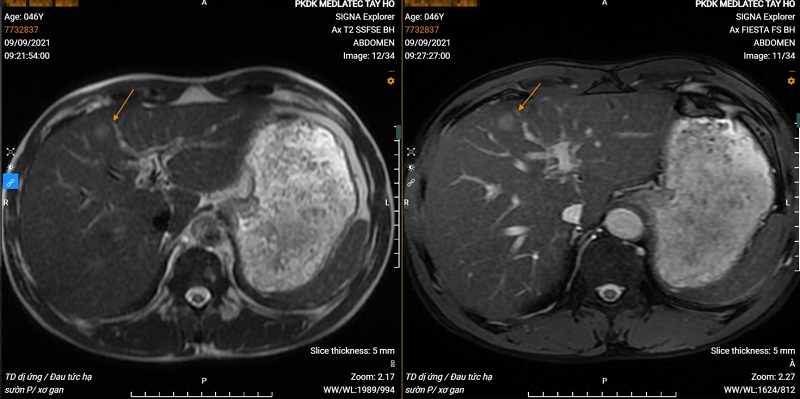

Hình ảnh khối u gan trái trên phim chụp MRI của bệnh nhân. |

Kết quả thăm khám cho thấy: Người bệnh không có hội chứng tăng áp lực tĩnh mạch cửa; hình ảnh X-quang có thoái hóa khớp gối hai bên; Hình ảnh siêu âm, chụp cộng hưởng từ thấy khối u hạ phân thùy S4 gan trái, kích thước 16x18mm, giàu mạch; Xét nghiệm chỉ số ung thư AFP 11.2 ng/mL; Kháng thể IgE 1.574 IU/mL.